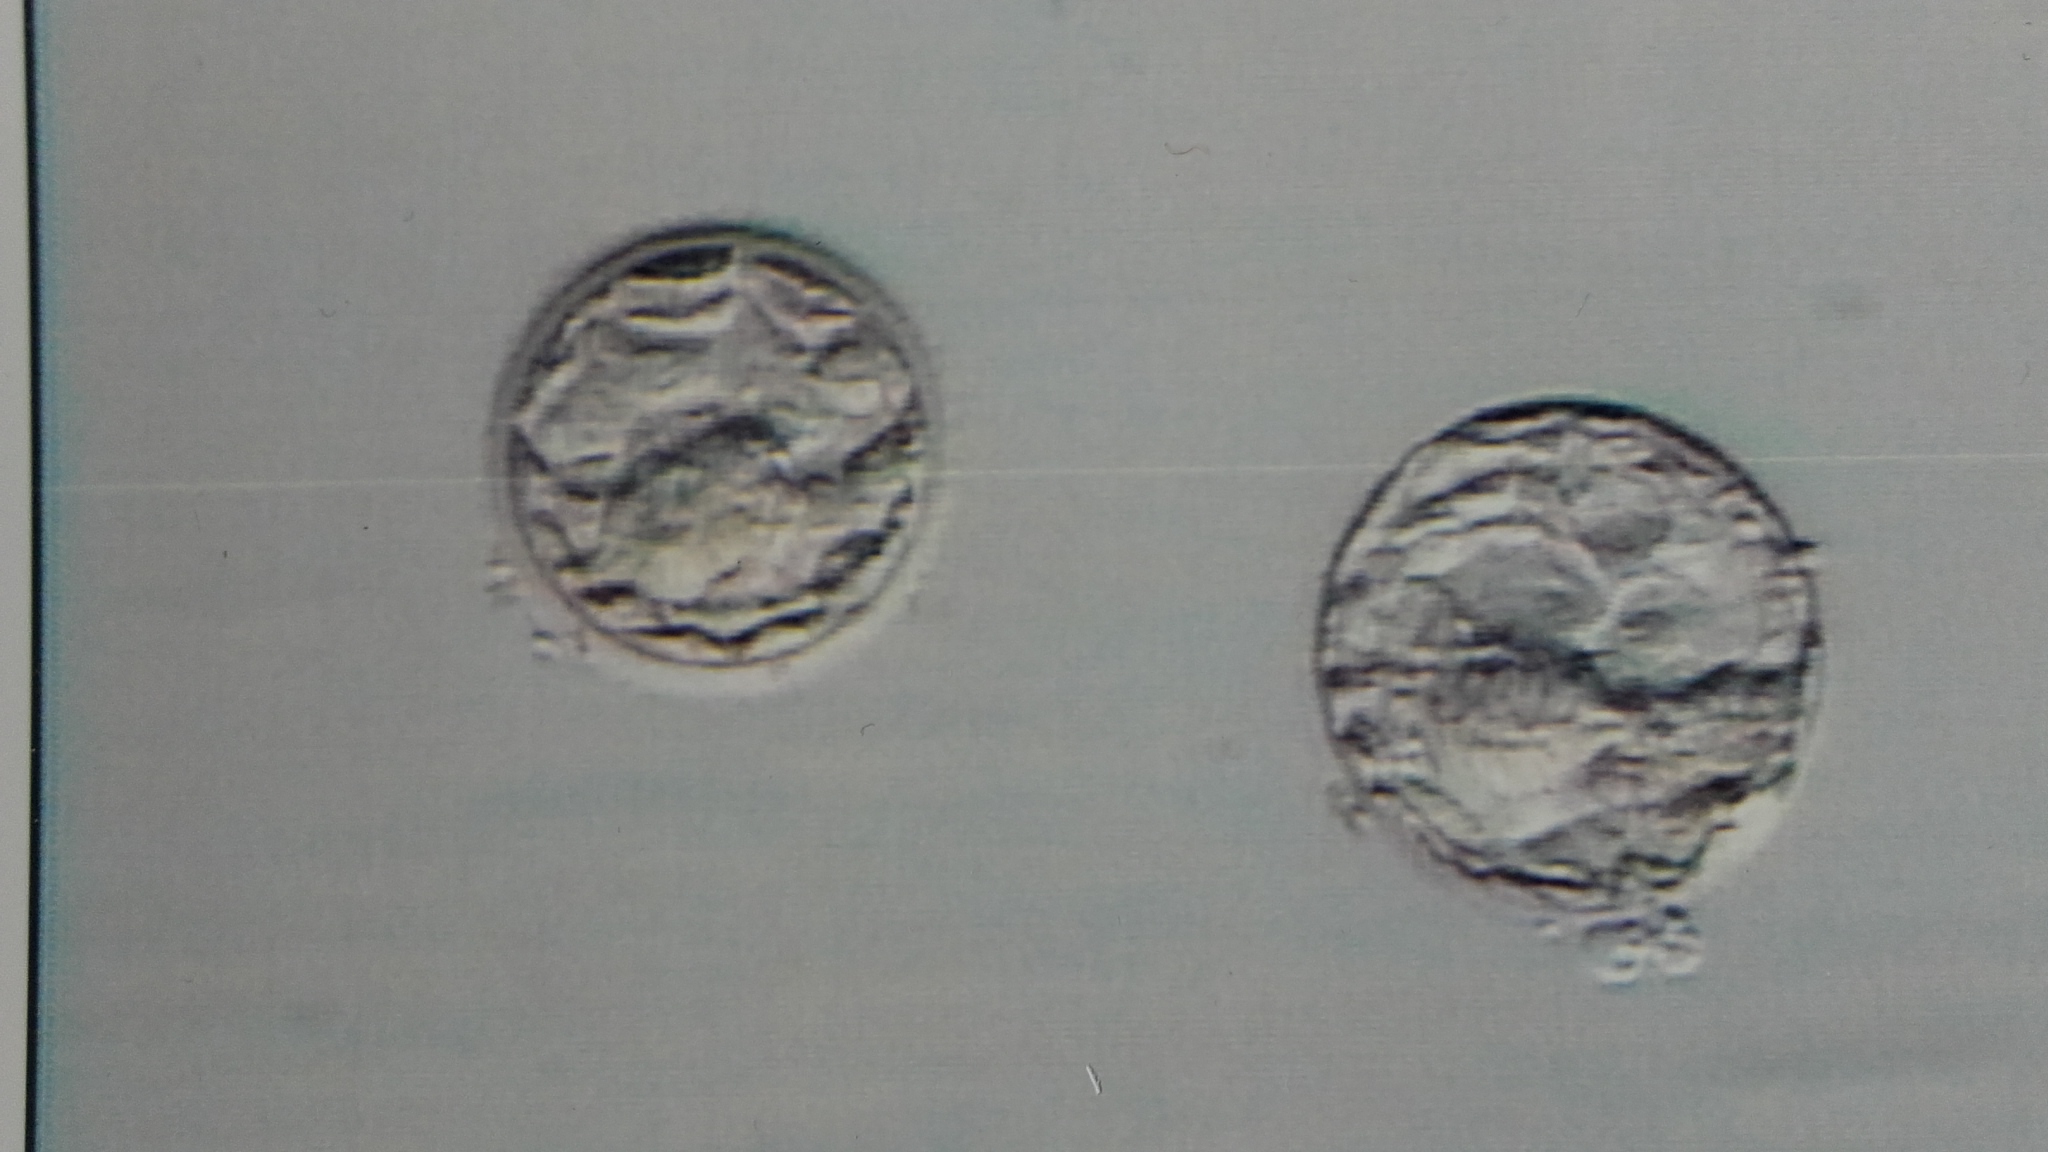

Im März/April wurde ich schwanger nach dem Transfer von 2 expandierten Blastozysten. 6 befruchtete EZ sind ins Rennen gegangen. Hier wurde ein Standard-Kulturmedium verwendet, da EmbryoGen/BlastGen nicht lieferbar war. Ich wurde zum ersten Mal schwanger (unteres Bild), leider war es ein Missed Abort mit Ausschabung in der 9. SSW wegen einer Trisomie 22.

Einen Monat nach der Ausschabung ein neuer ICSI-Versuch. Diesmal mit EmbryoGen/BlastGen. Es gingen nur 4 befruchtete EZ ins Rennen, an Tag 5 gab eine eine kompaktierte Morula und eine expandierte Blastozyste (oberes Bild). Es ging negativ aus.